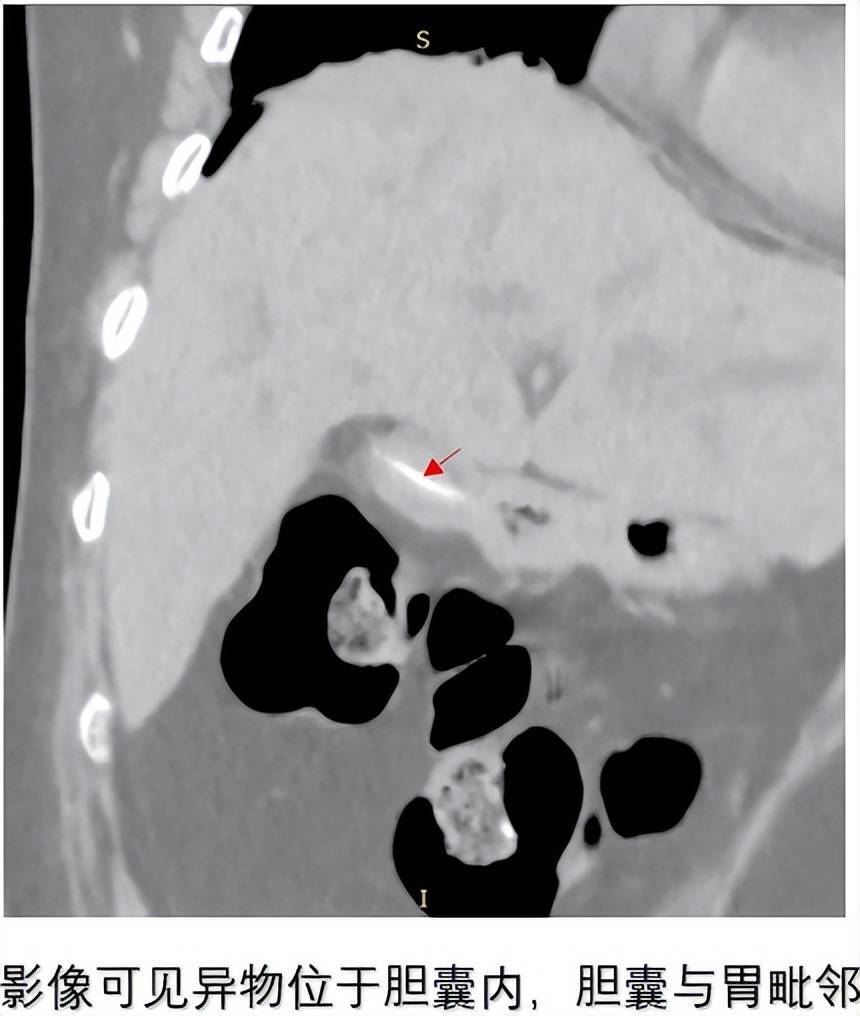

患者为79岁女性,因“间断上腹痛10月余,加重伴皮肤巩膜黄染、寒战发热3天”入院。既往有高血压病史5年,无手术史。入院后CT检查提示:胆囊结石、胆囊积气,胆囊内可见条索状高密度影,胆囊与胃毗邻,肝内外胆管扩张、胆总管下段结石。这种影像学表现高度提示可能存在胆囊胃瘘——一种临床上极为罕见的并发症。

面对罕见病例,开滦总医院肝胆外科二病区与CT室等相关专家立即展开深入讨论。结合患者CT显示的胆囊内金属密度影、胆囊积气以及胆囊与胃紧密连接的特征,专家团队高度怀疑存在胆囊胃瘘,同时合并胆囊结石、胆总管结石。经过充分论证,决定为患者实施腹腔镜探查+胆囊切除+胆总管切开取石+T管引流术,并做好术中处理瘘口的准备。